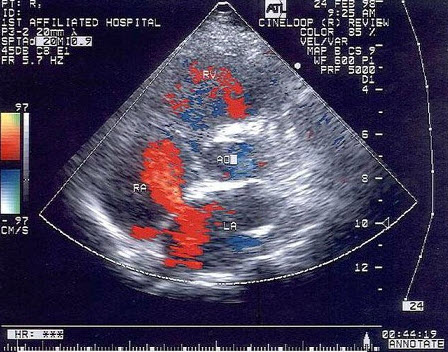

27、单项选择题

该病例最有可能诊断()

A.肺静脉畸形引流

B.上腔静脉型房缺

C.Ⅱ孔型房缺

D.卵圆孔重开

E.下腔静型房缺